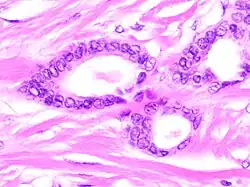

Histology

Tubular carcinomas are generally around 1 cm. or smaller, and are made up of tubules. They are usually low-grade.[2] Elastosis has been noted as common but is not present in all cases.[11]

A highly differentiated invasive carcinoma that forms well-defined tubules (containing epithelium, but no myoepithelium) and that have abundant desmoplastic fibrous stromal reaction between the tubules.